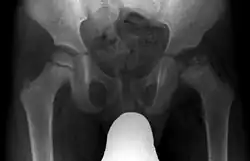

Beim Morbus Perthes handelt es sich um eine wahrscheinlich durch Durchblutungsstörungen hervorgerufene Erkrankung des Hüftkopfes im Kindesalter. Im Frühstadium führt sie zu einer Gelenkreizung mit Gelenkergüssen, so dass eine Ähnlichkeit mit rheumatischen Erkrankungen besteht. Im weiteren Verlauf tritt regelhaft ein Zusammensintern der Hüftkopfkugel auf, oft verbunden mit einem seitlichen Auswandern aus dem Gelenkkugellager im Becken, auch Gelenkpfanne. Später kommt es zu einer bleibenden Verformung von Kopf und Pfanne mit einer entsprechenden Bewegungsstörung. Das Bein bleibt verkürzt. Der frühe Verschleiß des Hüftgelenkes ist vorbestimmt. Bei Kindern im Alter von 2 bis 12 Jahren muss beim Auftreten von Hüftschmerzen und -hinken, bei Schmerzausstrahlung ins Knie und Gehfaulheit an diese Erkrankung gedacht werden. Mit Röntgenaufnahmen lassen sich die knöchernen, aber nicht die knorpeligen Veränderungen des Hüftgelenkes erkennen.

Typischer Verlauf im Röntgenbild

- Initialstadium: Scheinbare Gelenkspaltverbreiterung im Hüftgelenk.

- Infraktionsstadium: Subchondrale Infraktionslamelle „Konturdoppelung“

- Kondensationsstadium: In diesem Stadium ist eine Verdichtung der Knochensubstanz zu erkennen.

- Fragmentationsstadium: Ein scholliger Zerfall der Hüftkopfepiphyse wird erkennbar, mit Abflachung und eventuell Querverbreiterung und Herausragen des Hüftkopfes aus der Pfanne.

- Reparationsstadium: Es kommt zur allmählichen Wieder-Verknöcherung des Hüftkopfes.

- Ausheilungsstadium: Die Umbauprozesse sind abgeschlossen, unter Umständen liegt eine Deformierung des Hüftkopfes vor, wenn es in der Reparationsphase zu Fehlbelastungen gekommen ist.

Es kommt zur Einschränkung in der Abspreiz- und Drehbeweglichkeit im Hüftgelenk, so dass es zu einem positiven Viererzeichen kommt. Die Innenrotation und Abduktion sind eingeschränkt, später auch die Beugung und Streckung. Schmerzen sind nicht zwingend vorhanden, können sich aber im Verlauf sowohl im Hüft- als auch im Kniebereich als Ruhe-, Belastungs- oder Anlaufschmerz entwickeln. Frühsymptome sind z. B. ein u. U. diskretes Schonhinken und/oder Lauffaulheit. Im Röntgenbild lassen sich die oben genannten Veränderungen oft erkennen. Hierzu ist neben der Röntgen-Beckenübersicht immer auch eine 2. Ebene (axial, Lauenstein-Aufnahme) erforderlich[1] Als weiterführende Diagnostik wird meist eine Magnetresonanztomografie (MRT)-Untersuchung durchgeführt. Da die Initialphase meist nur wenige Wochen andauert, die Beschwerden sich aber häufig erst in der Kondensationsphase einstellen, kommt es auch erst dann zur Diagnose. Dann reichen Röntgenbilder in zwei Ebenen.